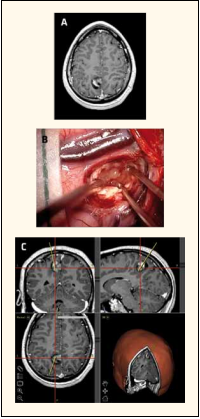

Lựa chọn phẫu thuật trong điều trị bệnh lý động kinh - Bệnh viện Việt Đức

Co giật, giảm trí nhớ, giảm thị lực: Những dấu hiệu thường gặp của bệnh lý u não bậc thấp - Bệnh Viện Việt Đức